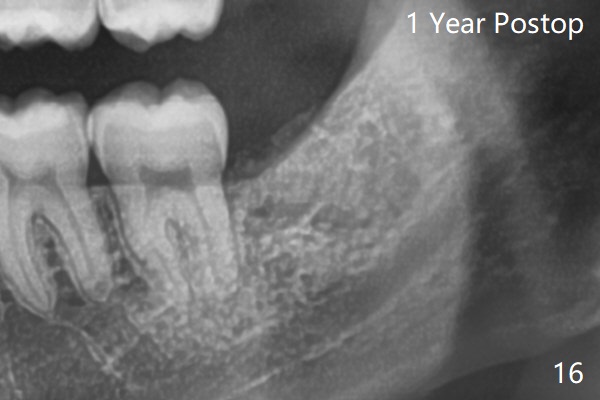

In fact the tooth #32 is extracted first; the defect involves the distobuccal aspect of the tooth #31 (Fig.4 *). An intraop PA is taken after extraction to confirm whether a broken surgical fissure bur tip retains or not; the distal lamina dura of #31 is low (Fig.5 *). It is expected to increase after cocktail bone graft (Fig.5' arrow). As planned, the bone cement (Fig.6 C) and allograft (G) are placed in the distal and mesial portions of the socket; between them is Osteogen Plug (O). Another piece of Osteogen Plug (as collagen membrane for bone graft) is placed on the top of the socket before suturing with 4-0 Plain Gut (Fig.7,7' O). Also note the bone graft being placed distobuccal (CT study) to #31 (Fig.7' red dashed line) to reduce possibility of future periodontitis. The patient returns 15 days postop with chief complaint of mild pain since extraction, although the wound looks normal. The transverse cortex connecting to the lamina dura (Fig.5 *) is obliterated when allograft is placed (Fig.7 G). The part of the graft remains in place 1 month postop (Fig.9) in spite of wound dehiscence (Fig.8). The bone graft loss is indicated by the fact of the reappearance of the transverse cortex (Fig.9). In the same appointment, the tooth #17 (Fig.10) is being extracted (Fig.11), leaving a defect mesiobuccal (Fig.12 *) to distal (curette). Part of Osteogen plug (Fig.13 O) is stretched to cover the mesially placed allograft (Fig.14 G). One quarter of Collagen plug is placed over the Osteogen plug (Fig.13 O) before 4-0 PGA suturing. There is bone regeneration 1 year postop (Fig.15,16).